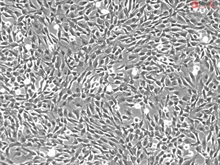

Human Annulus Fibrosus Cells, Passage 1

Degeneration of the intervertebral disk is a major pathological process implicated in low back pain. The causes of low back pain include genetics, environmental factors, and psychosocial factors. The anulus fibrosus makes up the peripheral portion of the disk structure, and is composed of fibrocartilage and type I and II collagen. Cells of the intervertebral disc are influenced by both biophysical and mechanical factors in their local environment. The anulus fibrosus cells can be stimulated by interleukin 1 beta to produce factors implicated in local degradative and inflammatory processes. Although mechanical stress is an important modulator of degeneration, the underlying molecular mechanism remains unclear. Human annulus fibrosus cells provide an in vitro model for the study of cellular and molecular events involved in disc degeneration, tissue engineering and cell therapy for spinal disc disorders. (SC4810)